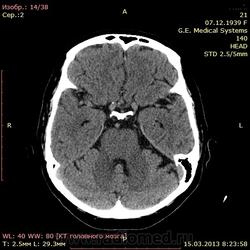

А как по мне, то тут геморрагический инсульт. Есть дислокация срединных структур слева.

Геморрагический инфаркт левой височной доли (в проекции таламуса слева) как правильно по локализации сам не знаю, скорее все таки таламус, со смещением срединных структур вправо, третий и левый боковой желудочек частично компримированы, формируется зона перифокального отека

тут либо геморрагический инсульт с перифокальным отеком, либо ишемический инсульт с геморагическим пропитыванием. Как их различить? Что скажут опытные коллеги?

Типичное медиальное кровоизлияние (в таламусе, медиальнее внутренней капсулы), уже не совсем свежее, плотность уже более низкая и зона отека приличная.

КТ признаки кровоизлияния в базальных ядрах, отделах с выраженными признаками перифирического отека. Про давность - сами пусть спросят , но скорее не свежак, до 5-6 дней.

Описывайте как геморрагический инсульт с объемным действием (смещением) на срединные структуры мозга. Померяйте плотности для оценки стадии. А различить на КТ две обговариваемые формы думаю нельзя. Разве что при пропитывании не будет такой четкой динамики изменения плотности очага. В литературе не встречал.